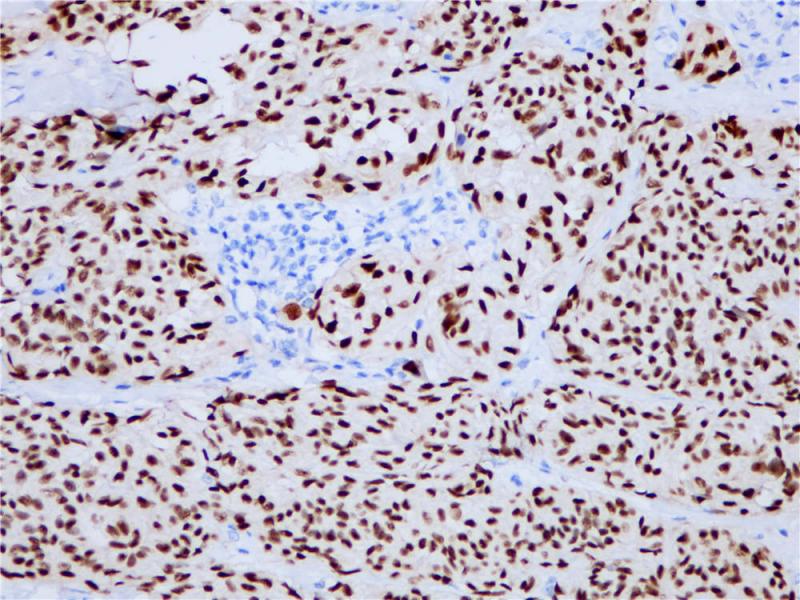

SOX10 重组兔单克隆抗体

阳性对照

黑色素瘤

亚细胞定位

细胞核